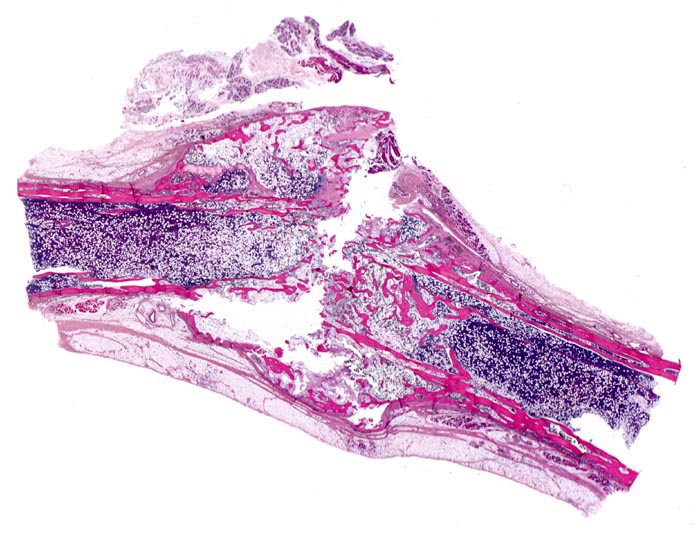

• Alte Rippenfraktur mit dislozierten Frakturenden. Sekundäre Frakturheilung mit Ausbildung eines fibroossären Frakturkallus.

• Extrem dünne Corticalis.

• Spongiosa ausserhalb der Fraktur mit ausgeprägter Osteopenie.

• Die Spongiosabälkchen sind stark verdünnt. Die Osteozyten innerhalb der Spongiosabälkchen sind eng zusammengerückt und die einzelnen Knochenlamellen sind ebenfalls verdünnt.

• Alterskorreliert normozelluläres Knochenmark.